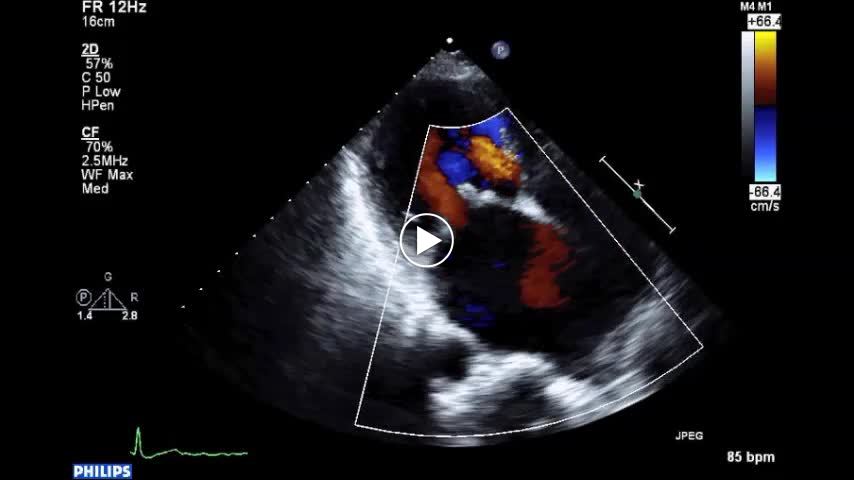

• 図8 リウマチ性MR(心房細動例) b 下